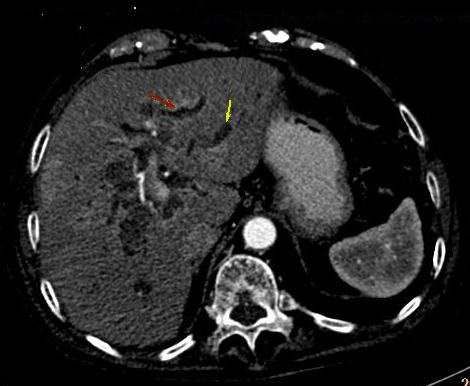

Image TDM :

Image TDM de la cholangite sclerosant

primitive est : Dilatation en discontinue a hypodensite des voies biliaires .

Image de hypertrophy a hypodense tres marquee du

lobe caudal du foie au stade cirrhosant , volume du foie peut etre grand

ou petit , sa bord est irregulier et en presence des

nodule calcifie ( hepatolithiasis ) .

Image de

dilatation systematise de voie biliaire

intrahepatique avec n'a pas de calcul

biliaire peut en susgestion de diagnostique

une CSP du foie |

|

Image radiologique d'une CSP en

coupe TDM axiale avec de conrtrast

intraveineuse . Aspect de dilatation et

stricture stenosant systematise des voies

biliaires intrahepatique . Foie

elargir et splenomegalie |

Dilatation systematise des voies biliaires

intrahepatique et de voie biliaire

commune avec des nodules calcifies (

hepatolithiasis ) . Aspect radiologique

a susgestion d'une cholangite sclerosant

primitive . Image TDM en coupe axiale

( non contrast ) |

Image de dialtation des voies

biliaires intrahepatique . Foie est elargir

et rude , veine porte dilate ,

splenomegalie , n' a pas de calcul biliaire

. Cholangite sclerosant primitive du foie en

coupe frontale ( TDM plus C+ ) |